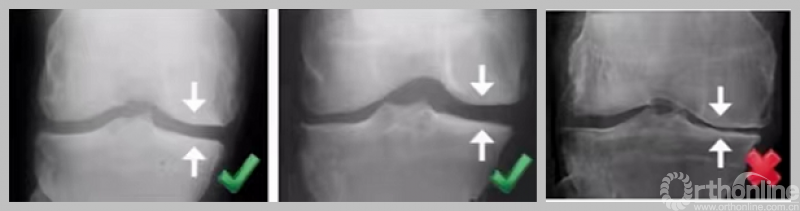

2. 骨对骨表现

负重位;内翻应力位。

3. 外侧全层软骨完好

负重位及外翻应力位保证外侧间隙正常。